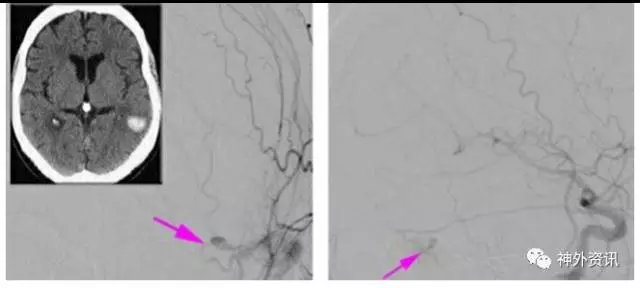

图2. 一例右侧筛骨dAVF(左图,箭头),位于前筛板水平。行右侧眉弓眶上开颅,暴露引流静脉(右图,箭头)。在大脑镰旁发现动脉化静脉,烧灼后离断。